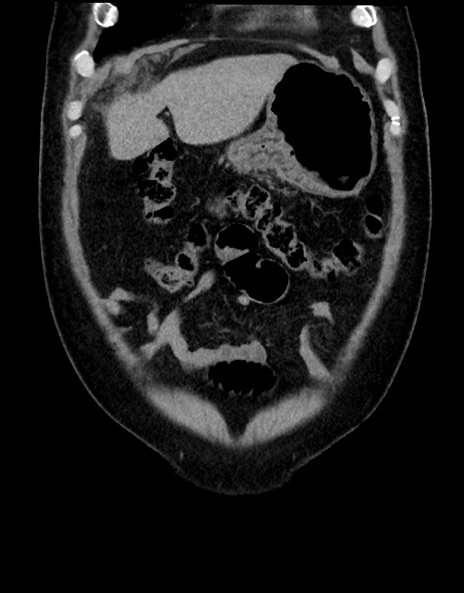

症例15(冠状断像)

【症例】70歳代男性

【主訴】腹痛

【現病歴】今朝から腹痛あり。全体的に痛い。特に左上の方。排ガスが今日はない。冷や汗が出る。

【既往歴】直腸癌術後

【身体所見】左側腹部〜上腹部に圧痛あり。腹膜刺激症状明らかなではない。軽度反跳痛。左下腹部に術後瘢痕あり。

【データ】WBC 7700、CRP 0.02